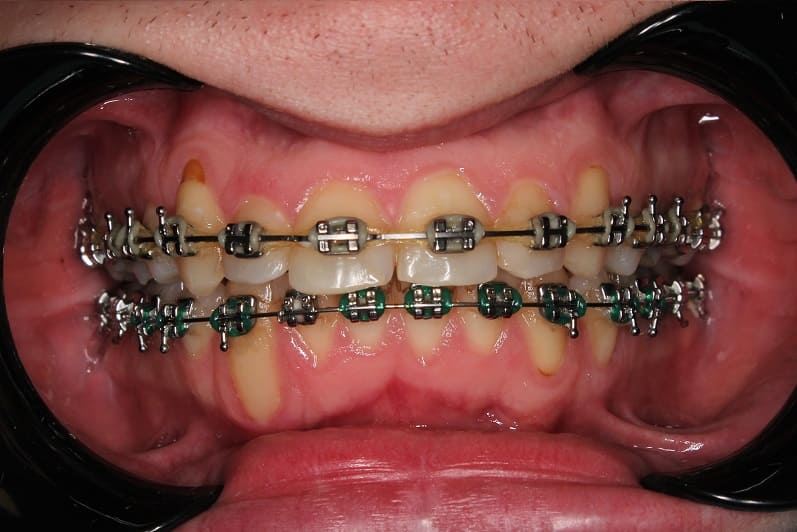

Ортодонтическое лечение на самолигирующейся брекет-системе

Ортодонтическое лечение на самолигирующейся брекет-системе заняло 2,5 года.